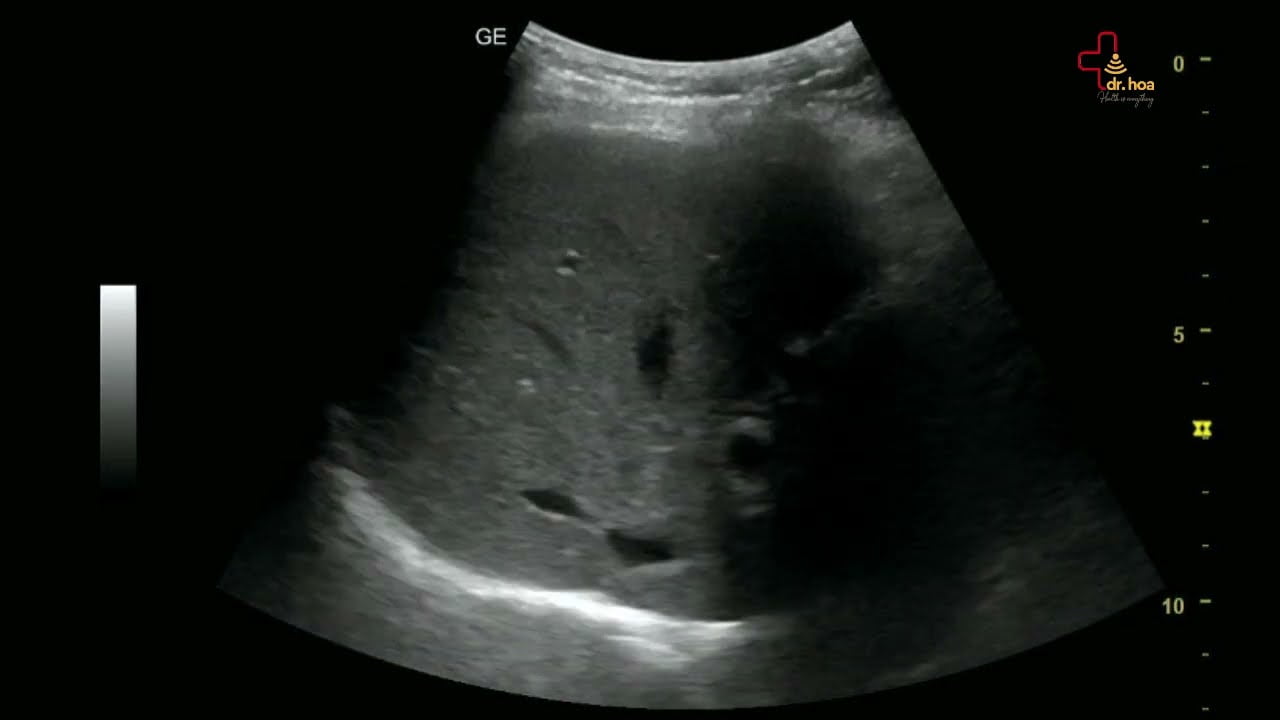

Sieu am Q7 xin gioi thieu case sieu am bung tong quat

Siêu âm Q7 xin giới thiệu case #siêu_âm_bụng_tổng_quát.